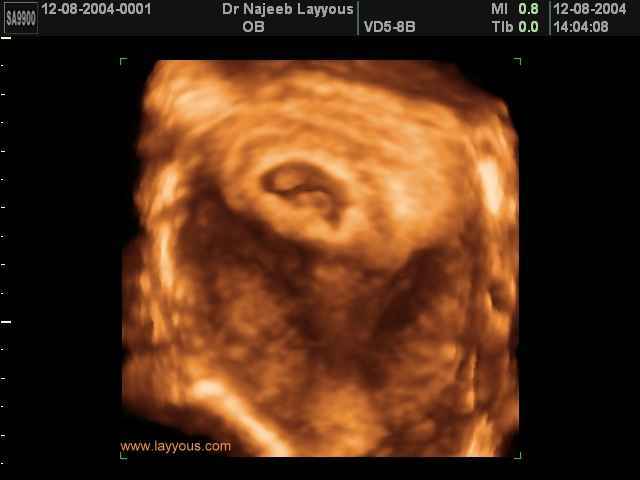

3D First Trimester Ultrasound Scan Photos